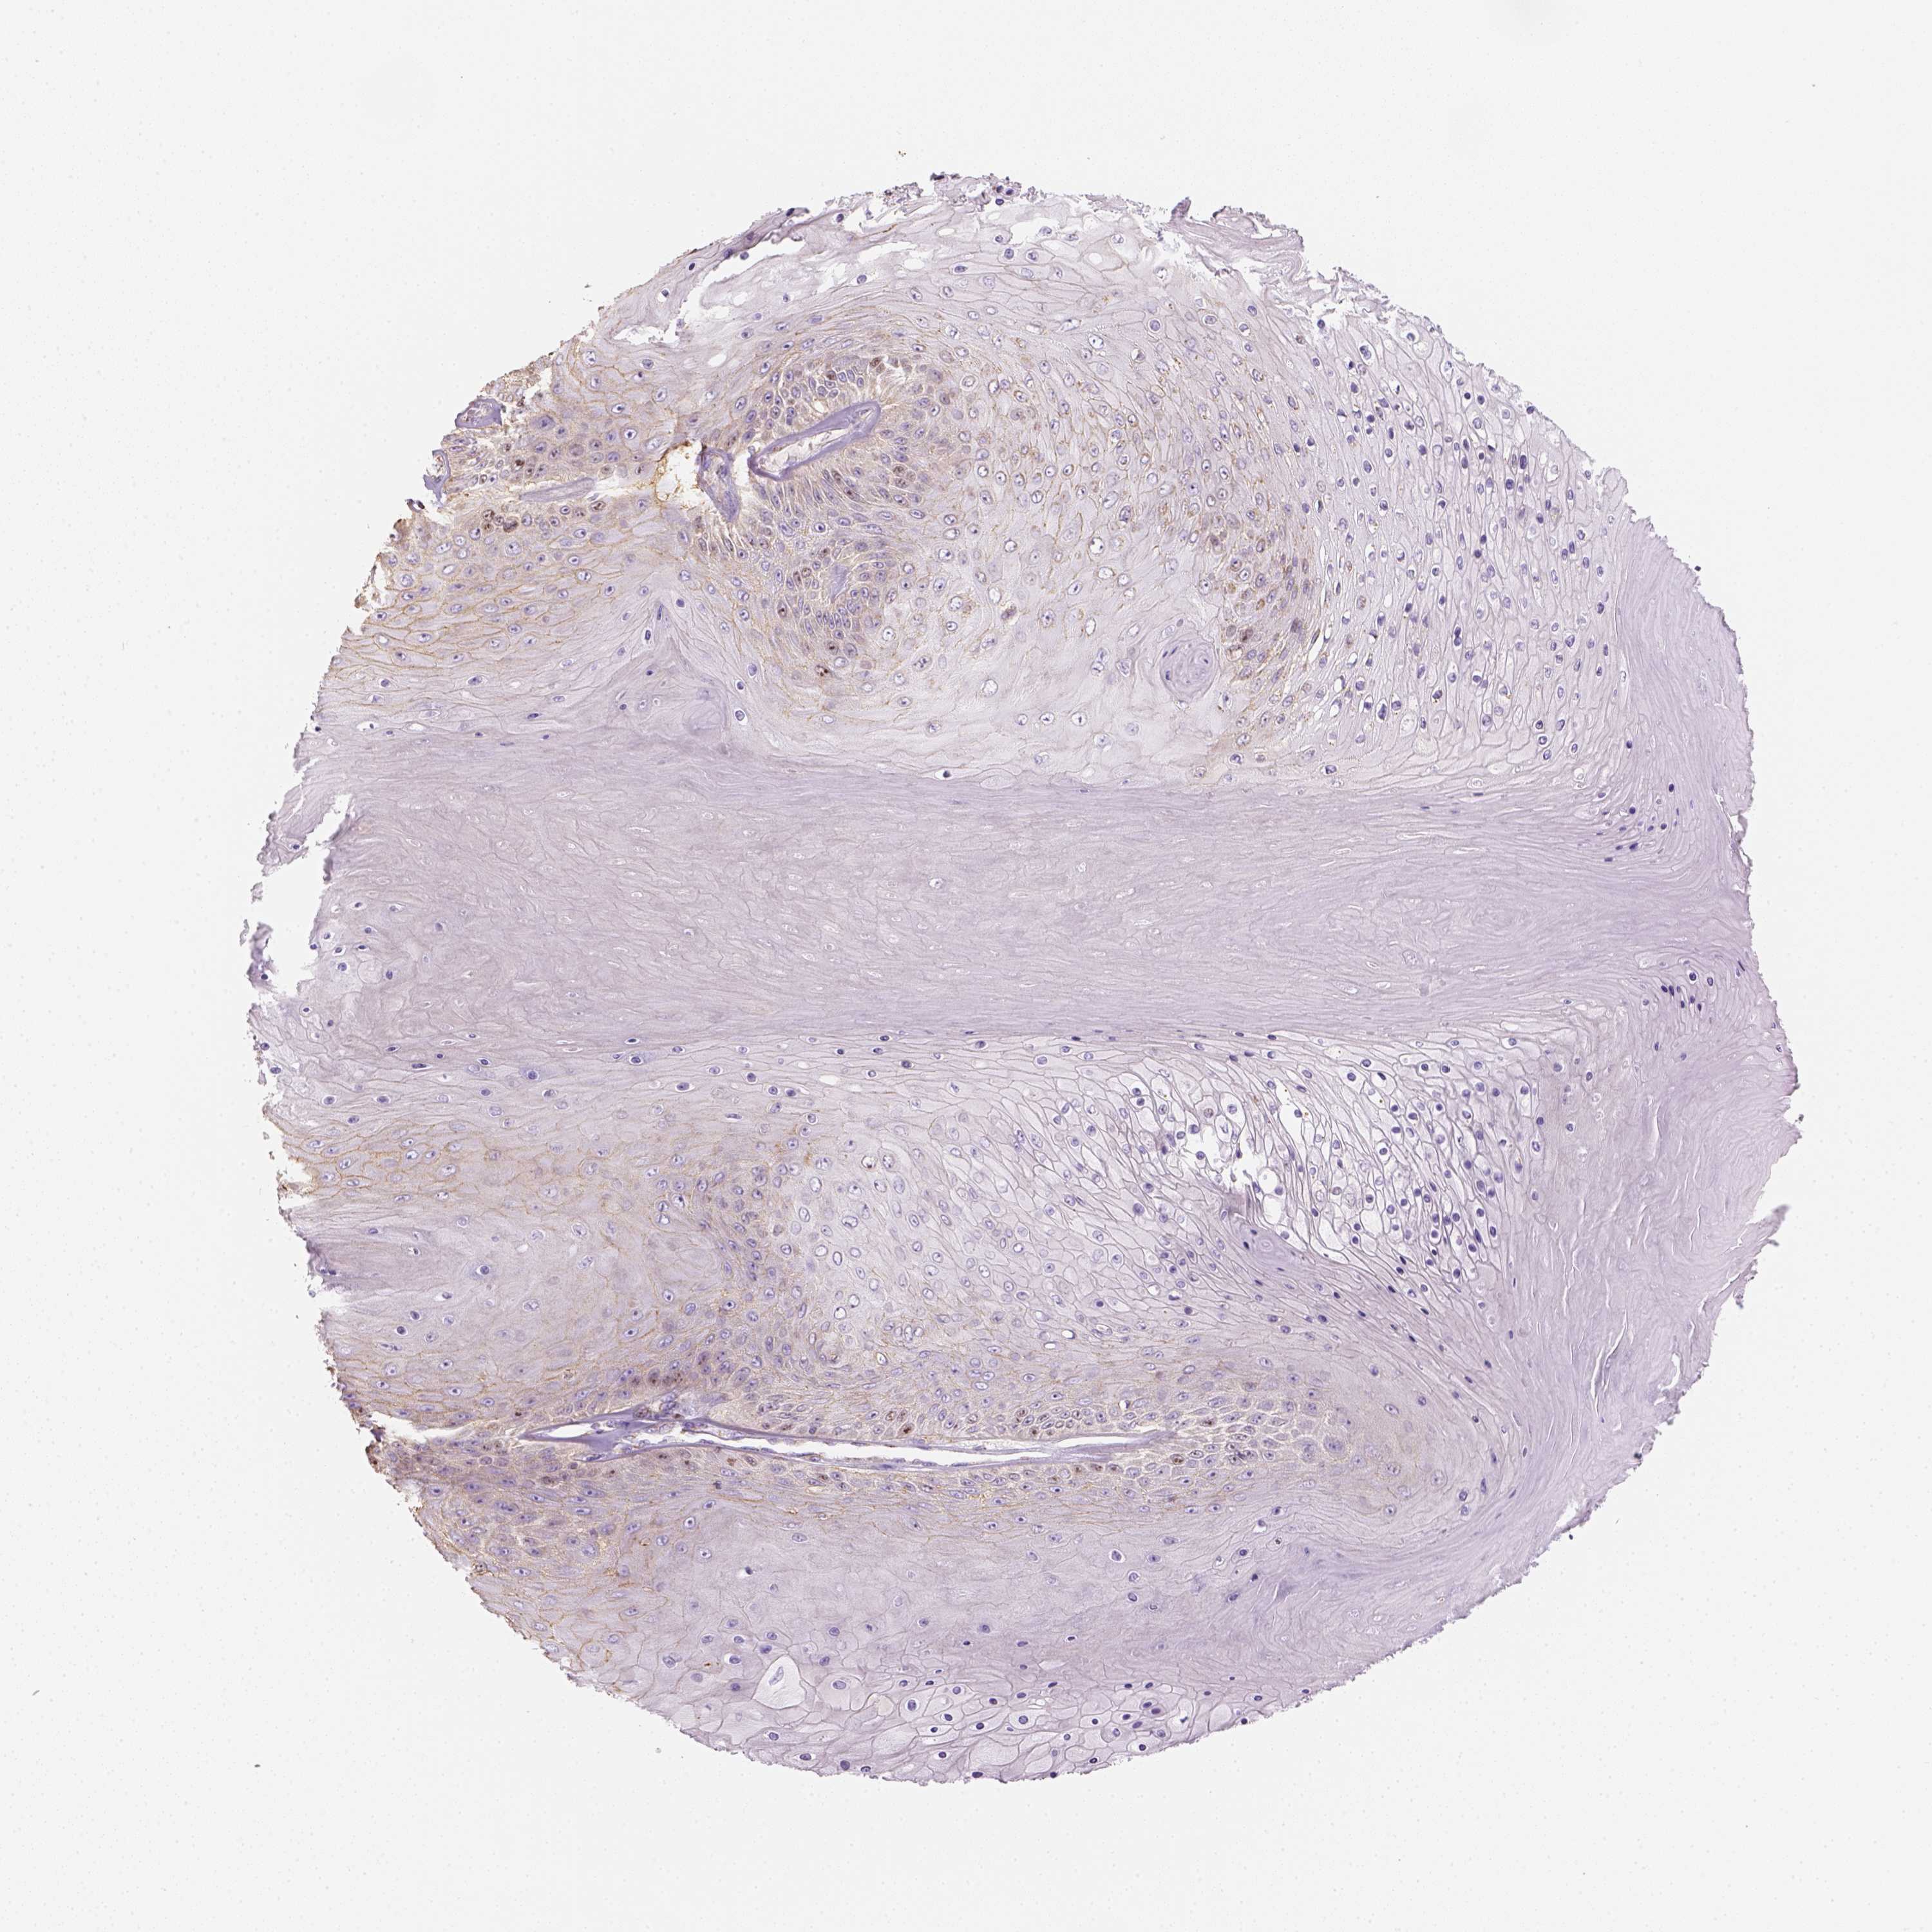

Basal cell and squamous cell cancer

SKIN CANCER - Protein expressioni

A mouse-over function shows sample information and annotation data. Click on an image to view it in a full screen mode. Samples can be filtered based on level of antibody staining by selecting one or several of the following categories: high, medium, low and not detected. The assay and annotation is described here.

Antibody stainingi

Antibody staining in the annotated cell types in the current human tissue is reported as not detected, low, medium, or high, based on conventional immunohistochemistry profiling in selected tissues. This score is based on the combination of the staining intensity and fraction of stained cells.

Each image is clickable and will lead to virtual microscopy that enables deeper exploration of all samples and also displays staining intensity scores, fraction scores and subcellular localization as well as patient and tissue information for each sample.

Antibody HPA029053

Antibody HPA029055

Staining

High

Medium

Low

Not detected

Intensity

Strong

Moderate

Weak

Negative

Quantity

>75%

75%-25%

<25%

None

Location

Nuclear

Cytoplasmic/membranous

Cytoplasmic/membranous,nuclear

Squamous cell carcinoma, NOS